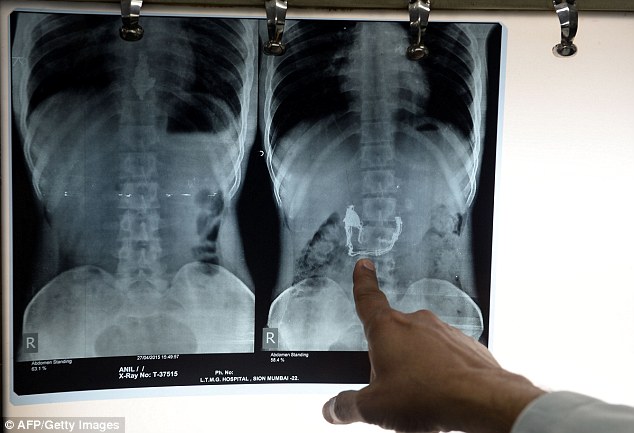

E' stato costretto a mangiare oltre 60 banane e a subire quattro clisteri, e tutto perché aveva ingoiato una collana d'oro del valore di qualche migliaio di euro. E' successo a Mumbai, in India, a un presunto ladro che, catturato dalla polizia, ha a lungo negato di aver rubato il gioiello, tanto che gli agenti stavano per crederci. L'uomo, infatti, dopo aver sottratto la collana a una donna l'ha repentinamente messa in bocca e mangiata, nella convinzione che in questo modo sarebbe stato molto difficile incastrarlo. Non sapeva, evidentemente, che la polizia era disposta a sottoporlo a una radiografia all'intestino, che puntualmente ha confermato il furto. E' così che al ladro è stato imposto di bere un liquido speciale e mangiare una sessantina di piccole banane, nella convinzione che ciò avrebbe semplificato la digestione e facilitato l'"espulsione" del gioiello.